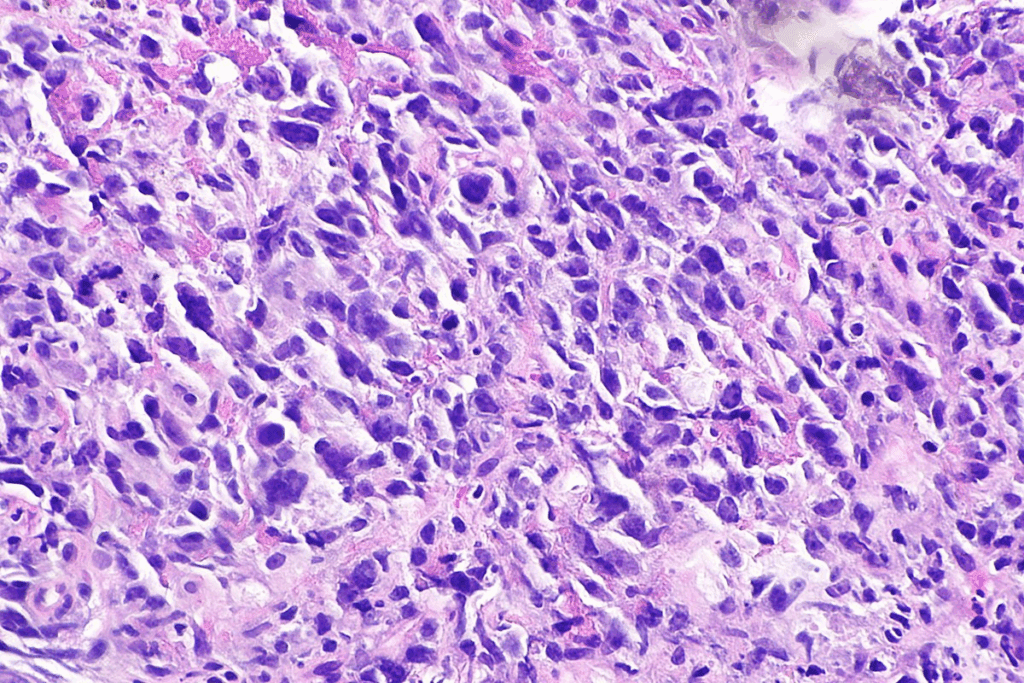

Types of Lung Cancer

Lung cancer is mainly split into two types: Non-Small Cell Lung Cancer (NSCLC) and Small Cell Lung Cancer (SCLC). NSCLC makes up about 85% of cases, with subtypes like adenocarcinoma and squamous cell carcinoma. SCLC is more aggressive and often linked to smoking.